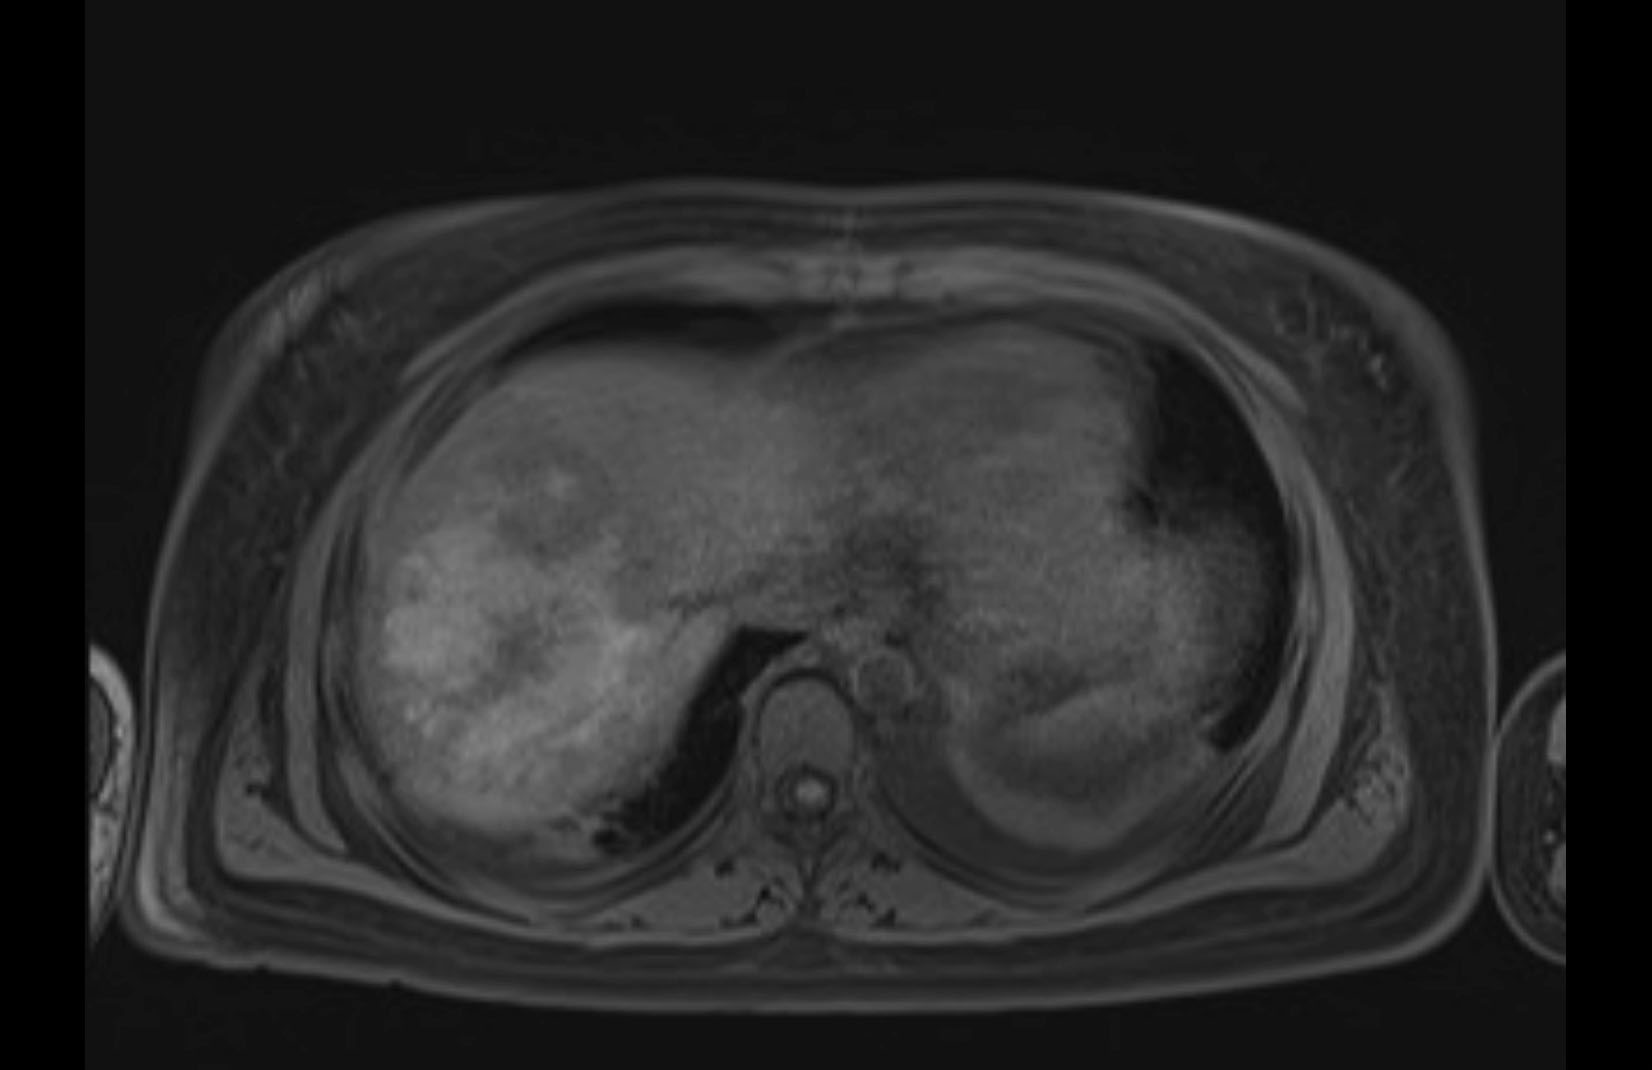

Imaging Analysis

Look through the patient's CT scan to identify any areas of concern for the necessary procedure.

MRI T1

MRI T2

Based on initial findings, which issue(s) would you be most concerned about?